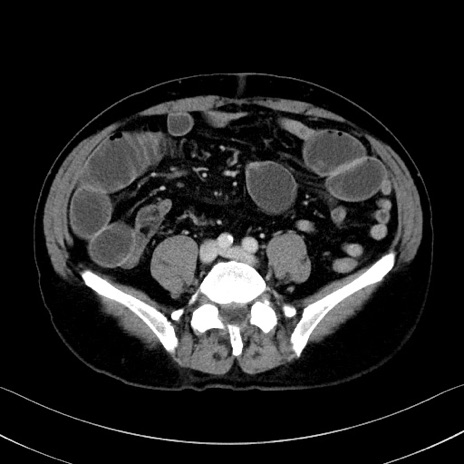

症例35(横断像)

【症例】70歳代 男性

【主訴】腹部膨満、嘔吐

【現病歴】昨日より腹部膨満感出現。本日増悪し、仙痛出現。嘔吐あり、受診。

【既往歴】糖尿病、胆摘後

【身体所見】BP 149/80mmHg、HR 74/min、BT 35.9℃、腹部:膨満、軟、圧痛なし。腸雑音減弱あり。上腹部正中切開瘢痕あり。

【データ】WBC 13500、CRP 1.72